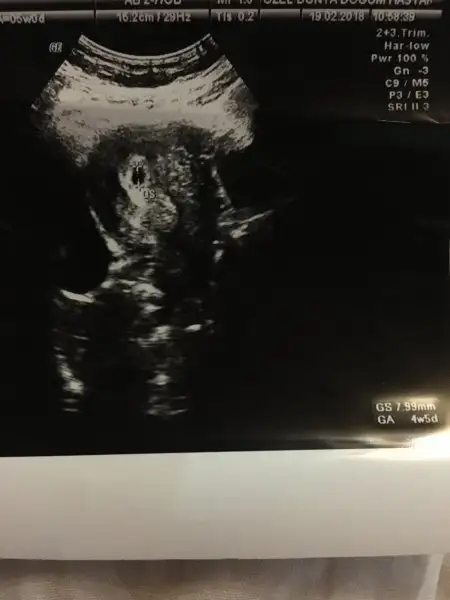

canım doktorum bana yolk kesesi için bişey söylemedi iki hafta sonra kalp atısı için gel dedi sadece bir bakar mısın varmı yolk kesesi ben anlamıyorum dadoğru cnm yolk kesesi gözükmezse o gebelık boş gebelık oluyor yolk kesesi çok önemlı

bir de yolk kesesi göründülten 1 hafta sonra da kalp atışı duyulmalı ... Benım pazartesi günü yolk kesesi göründü , doktor 1 hafta sonra tekrar çağırdı kalp atışı için

cnm ben burdan anlıyamam doktorum bana yolk kesesinin normal kesenın yanında olan beyaz bir yer olarak gösterdi ufaktı zaten dikkatli bakınca anlıyabıldım... Birsey demediyse yolk kesesi vardır ve hersey yolundadır.. Yolk kesesi olmadığı zaman zaten söylüyorlarcanım doktorum bana yolk kesesi için bişey söylemedi iki hafta sonra kalp atısı için gel dedi sadece bir bakar mısın varmı yolk kesesi ben anlamıyorum da

Evet canım keseyi gormekte diger kontroller kadar onemli ve guzel haberlerle dönmüşsün :)